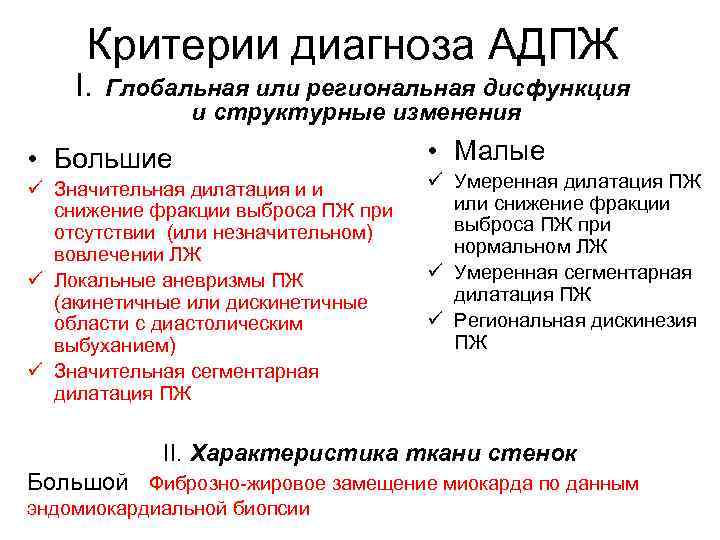

Критерии диагноза АДПЖ I. Глобальная или региональная дисфункция и структурные изменения • Большие ü Значительная дилатация и и снижение фракции выброса ПЖ при отсутствии (или незначительном) вовлечении ЛЖ ü Локальные аневризмы ПЖ (акинетичные или дискинетичные области с диастолическим выбуханием) ü Значительная сегментарная дилатация ПЖ • Малые ü Умеренная дилатация ПЖ или снижение фракции выброса ПЖ при нормальном ЛЖ ü Умеренная сегментарная дилатация ПЖ ü Региональная дискинезия ПЖ II. Характеристика ткани стенок Большой Фиброзно-жировое замещение миокарда по данным эндомиокардиальной биопсии

Критерии диагноза АДПЖ I. Глобальная или региональная дисфункция и структурные изменения • Большие ü Значительная дилатация и и снижение фракции выброса ПЖ при отсутствии (или незначительном) вовлечении ЛЖ ü Локальные аневризмы ПЖ (акинетичные или дискинетичные области с диастолическим выбуханием) ü Значительная сегментарная дилатация ПЖ • Малые ü Умеренная дилатация ПЖ или снижение фракции выброса ПЖ при нормальном ЛЖ ü Умеренная сегментарная дилатация ПЖ ü Региональная дискинезия ПЖ II. Характеристика ткани стенок Большой Фиброзно-жировое замещение миокарда по данным эндомиокардиальной биопсии